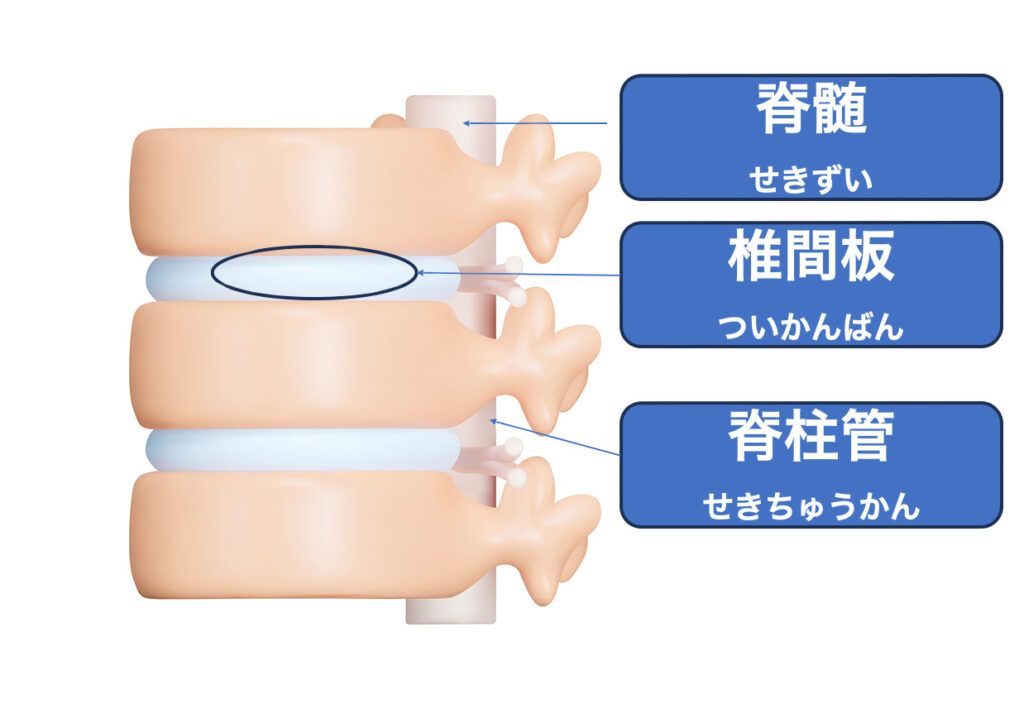

脊髄損傷は、脊椎(背骨)内部の輪状の空間が連なって形成する脊柱管の中にある脊髄が傷つく病状を指します。これは、交通事故などによる外的な強い力が原因で起こることが多いです。

また、脊髄腫瘍や椎間板ヘルニアなども、脊髄の炎症や血管の異常が起こると脊髄損傷と同じような症状を引き起こすこともあります。